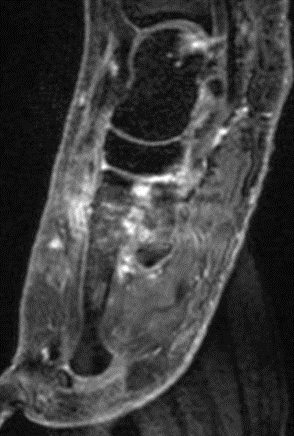

Abbildung 8.8.a bis d: Patientin mit bekanntem Knick-Senk-Fuß. Anamnestisch Schmerzen in beiden Füßen, links > rechts seit ca. 2 Jahren. Fragestellung: Status der bekannten Fußwurzelarthrosen vor geplanter OP. Neben, unter anderem fortgeschrittenen Arthrosen im Naviculo-Cuneiforme-Gelenk, Nachweis einer Tibialis posterior-Sehnen-Tendinitis mit begleitender Periostitis/Ostitis am Malleolus postero-medial. Abbildung 8.8.a und b: in der Frühphase (2 Minuten nach Tracerinjektion) sind lineare Anreicherung des Tracers im Verlauf der linken Tibialis posterior Sehne zu sehen.  In der  Mineralisationsphase im SPECT/CT begleitende Periostitis/Ostitis am Malleolus postero-medial. Abbildung 8.8.c und d: Der Blick auf das CT im Weichteilfenster offenbart diffuse entzündliche Verdickungen im Verlauf der linken Tibialis posterior Sehne. Rechts unauffälliger Befund. Unten beispielhaft die schmerzhafte NC-Arthrose.

Abbildung 8.9. a bis c: Extern MRT-morphologisch V. a. Coalitio calcaneo-naviculare. Anamnestisch Schmerzen im linken OSG seit ca. 1,5 Jahren, gehäuftes „Umknicken“ des linken Fußes, Pes planus bds.. Abbildung 8.9.a zeigt die 3D-Früh-SPECT aus verschiedenen Blickwinkeln. Wie in Abbildung 8.8.a findet sich hier eine deutliche lineare Tracerakkumulation im Verlauf der linken Tibialis posterior Sehne. Abbildung 8.9.b: In der Mineralisationsphase wie auch im vorhergehenden Fall ossäre Reaktion postero-medial am Mallelolus medialis als Zeichen einer chronischen Tendinitis. Die Durchsicht der 7 Wochen zuvor angefertigten externen MRT bestätigte den Befund (er war leider nicht beschrieben worden). Im SPECT/CT wurde eine Coalitio ausgeschlossen.